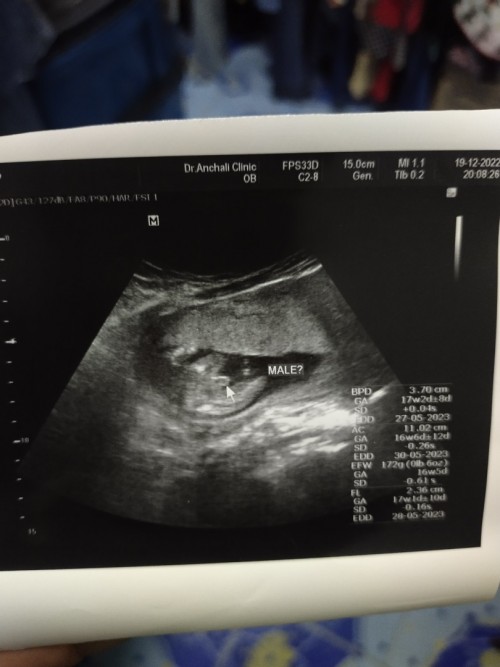

ฝันสลายเมื่อหมอบอกเพส😂

ธีมเดียวกันคะ ได้ เพศชาย👶🏻👶🏻👶🏻

บ้านนี้ชายค่ะอ้าขาโชว์เลยค่ะ